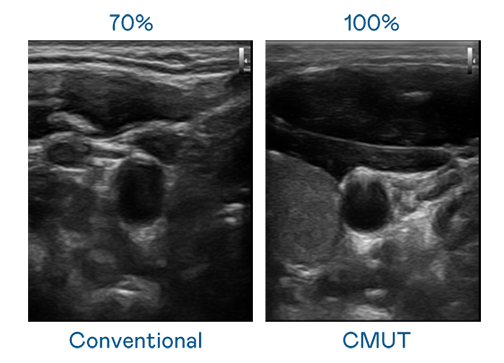

CMUT 技术是一种用电容式微机电元件来产生超音波讯号的技术。与传统 PZT 压电式技术相比,CMUT 频宽增加 30%,更宽频的超音波讯号让影像解析度大幅提升,是实现高影像品质医疗超音波扫描、促进精准医疗发展的关键技术。

超音波影像的解析度高低,首先取决于探头能发出的讯号频宽。91nba高清免费观看 CMUT 可提供高清晰的超音波讯号,提供高频宽、高灵敏度、影像纹理细节更高的超音波影像,协助医护人员缩短影像判读时间及利用精准的医疗影像进行诊断。